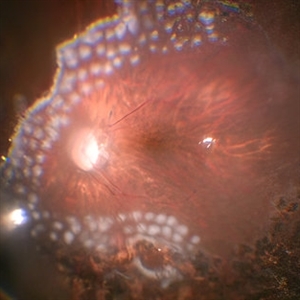

RPE rip in a case of Idiopathic polypoidal choroidopathy RPE rip in a case of Idiopathic polypoidal choroidopathyOct 23 2022 by Anjana Mirajkar, MS Ophthalmology OCT image in a of 61 year old male with RPE rip in a case of Idiopathic Polypoidal Choroidopathy. Photographer: Dr. Anjana Mirajkar -Retina Foundation, Ahmedabad Condition/keywords: Idiopathic polypoidal choroidopathy, RPE rip